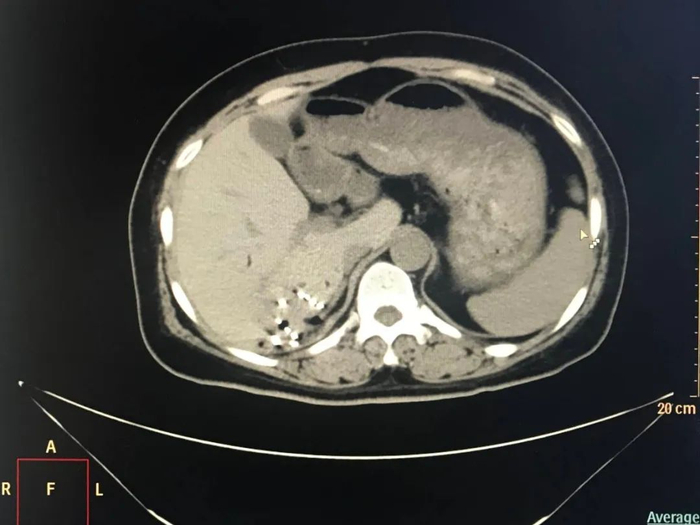

2023年4月,患者复查肝脏MRI显示病灶较前(2023年2月)增大。为了进一步控制患者病情,邢台市第九医院肿瘤内科一区团队会诊后,决定对她实施放射性粒子植入治疗。2023年5月,患者接受了CT引导下肝恶性肿瘤放射性粒子植入治疗,术后恢复良好。

放射性粒子植入术属于近程放疗,通常在超声或CT引导下进行,主要将125I粒子由细针直接穿刺至肿瘤并植入内部,通过其放射特性摧毁肿瘤。其优点在于125I粒子的射程较短、局部剂量高,便于把射线控制在肿瘤灶内,从而减少了射线对正常组织的损伤[1]